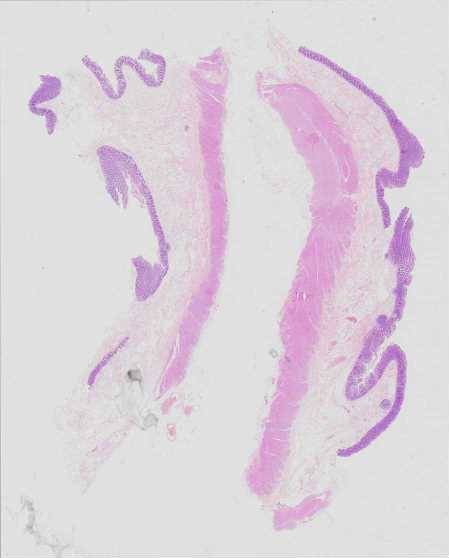

Use Case 2

041717172507

Overview Statistics B details